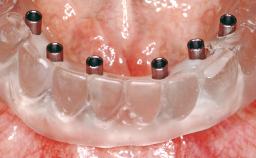

Conventional Loading of Eight Implants in the Maxilla and Final Restoration with a Full-Arch Gold-Ceramic FDP

# of Implants 8

Prosthesis Type FDP

Defining Characteristics Fully edentulous upper jaw to be rehabilitated with an implant-borne fixed dental prosthesis

Loading Protocol Conventional or early